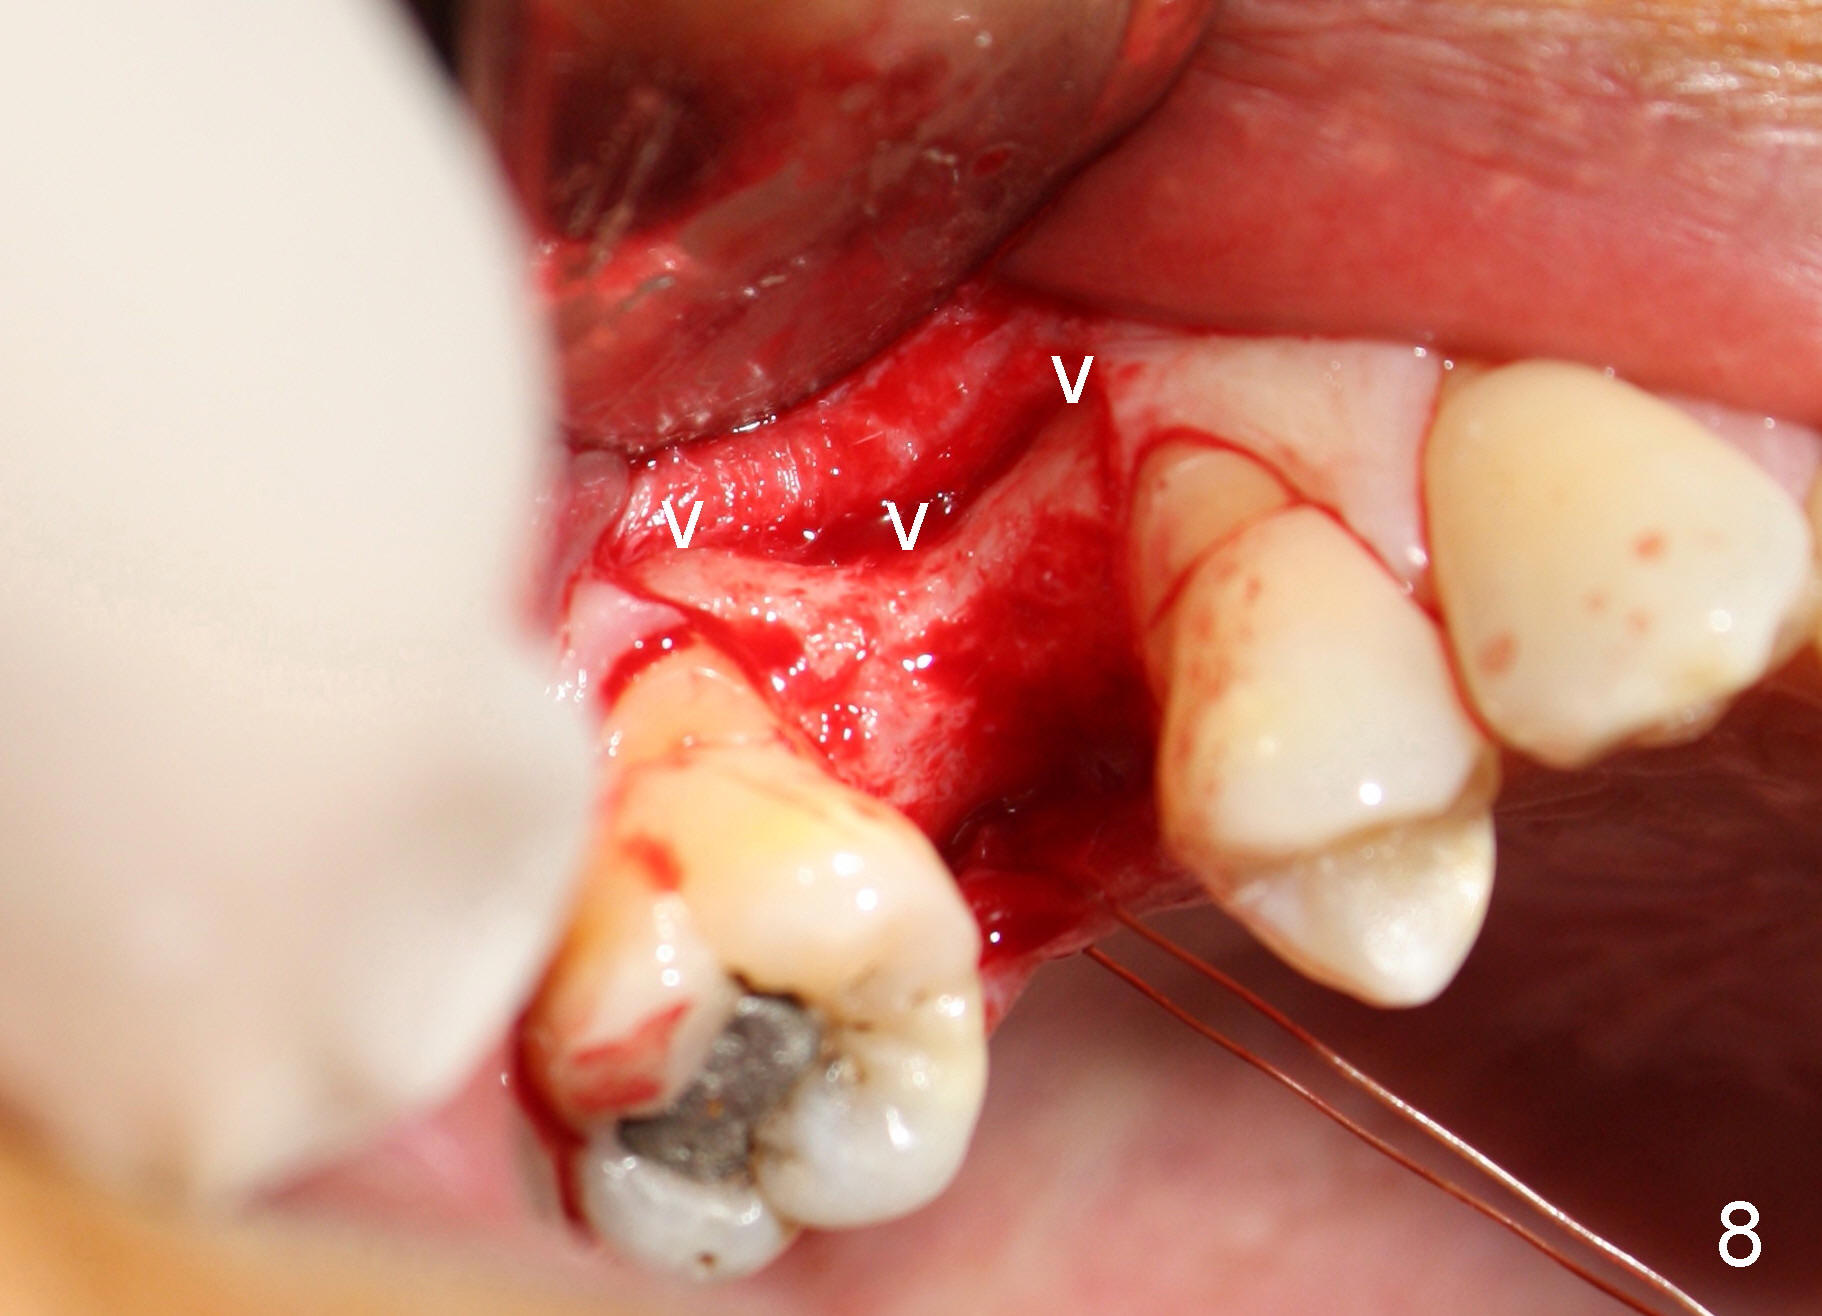

Nine months later, the patient returned for re-implantation (Fig.7). Amoxicillin and Chlorhexidine were used preop and postop. Flaps were raised for better vision of reimplantation site (Fig.8). Bone density was high (type II). Drills were used to form osteotomy (Fig.9). A 4x17 mm implant was placed with internal sinus lift (Fig.10*). The insertion torque was also >60 Ncm. The flaps were approximated and a short abutment (Fig.11 A) was placed to hold perio dressing in place.